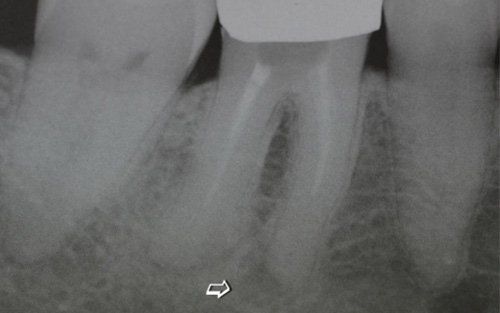

This treatment should be reserved for teeth that have irreversible pulp pathology (the nerve of the tooth) or an infection of the dental canals that has caused an abscess (acute apical periodontitis) or a granuloma (chronic apical periodontitis). While in the first two cases the tooth is very painful and the patient immediately seeks the dentist, the case of the chronic form is often silent, and therefore the patient may not notice anything for a medium to long period of time. In such conditions, it is only an X-ray image, taken during routine check-ups, that detects its presence. Root canal therapy can be completed by placing a latest-generation post inside the canal, as a means of retaining the material used for the reconstruction of the tooth. It will be up to the clinician to decide whether or not the restoration requires this additional anchoring system.